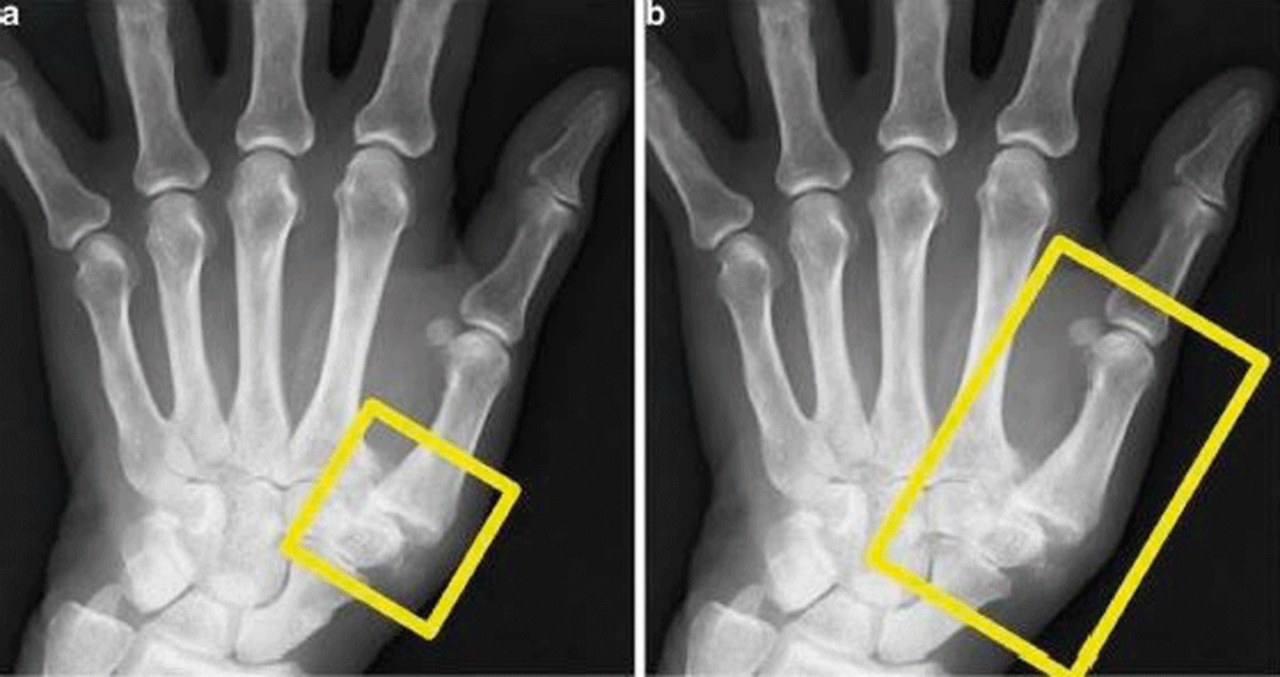

Dieser Patient mit Rhizarthrose bekommt das Daumensattel- und Daumengrundgelenk bestrahlt. Dieser Patient mit Rhizarthrose bekommt das Daumensattel- und Daumengrundgelenk bestrahlt. © Schneider T, Schneider­ K. internistische praxis 2019; 61: 284-300 © Medien­gruppe Oberfranken - Fachverlage GmbH & Co. KG, Kulmbach